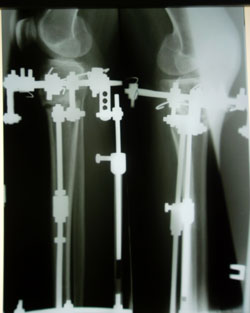

перед крутками.